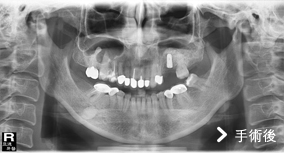

患者左上第一大臼齒缺牙,齒槽骨高度只剩下3公釐高度,但植牙需要至少10公釐高度的齒槽骨才能建造穩固的植體。

這種狀況下,可依患者狀況評估以「上顎竇增高術」,利用手術器械將「上顎竇膜」分離並提高,並填入骨粉,增加骨頭高度。因為竇膜易破,如傷到破損可能造成的併發症包括:上顎竇膜破裂、鼻竇炎、口腔與鼻竇相通、骨粉或植體感染,因此「上顎竇增高術」屬於較複雜的手術技巧,建議選擇臨床經驗豐富的醫師來操作較為適當。

手術後照片可以明顯看出齒槽骨高度已經增加,確定有足夠骨頭再植入一個植體,也順利替患者解決缺牙所帶來的不便。